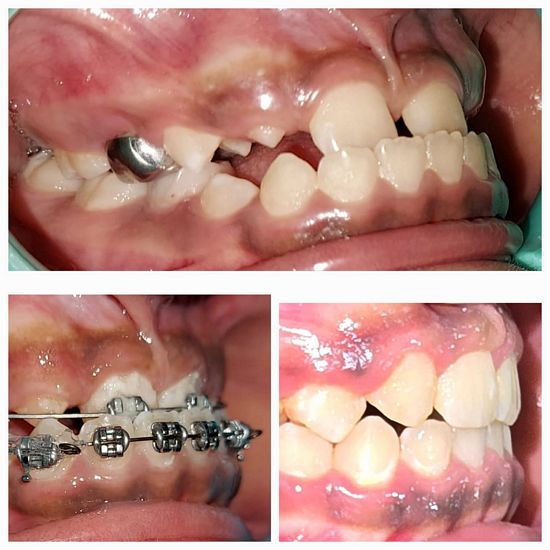

Dr. Jaipal Reddy is an experienced and highly regarded dental surgeon and cosmetic dentist based in Koramangala, Bengaluru. He is the founder and lead dentist at JP Dental Clinic, a well-established dental practice known for comprehensive, patient-centric oral care. Dr. Reddy holds a Bachelor of Dental Surgery (BDS) degree from the Government Dental College and Research Institute, Bangalore, and brings over 25 years of clinical experience in general dentistry, endodontics, and cosmetic dental procedures.